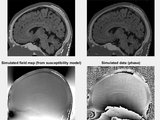

FORECAST is a fast alternative to Bloch simulation for simulating off-resonance effects in steady-state MRI. FORECAST accelerates simulation of steady-state pulse sequences by using multiple Fast Fourier Transforms to evaluate the signal equation, which can currently include proton density, T2, and off-resonance effects. Currently the simulation is limited to Cartesian pulse sequences, but we plan to add support for non-Cartesian pulse sequences.

- Simulation of susceptibility artifacts around air and metal.

- Simulation of a brainweb dataset, including T1, T2, susceptibility, and water-fat shift (Matlab R2015A or later required to automatically download the dataset)